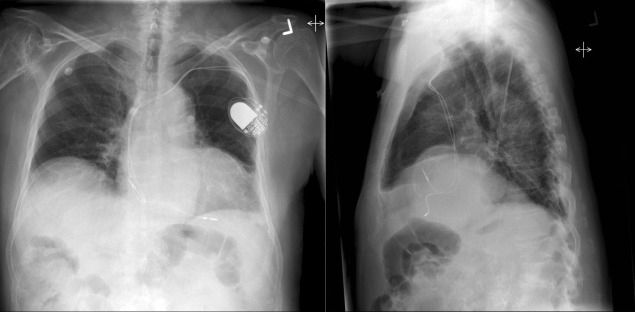

Pericardial calcification ( Figs. 27-1 to 27-4 ) is most prominent in the interventricular and atrioventricular grooves, and lateral to the right atrial and ventricular walls ( Graphic 27-1 ). When looking for pericardial calcification, it is necessary to scrutinize the lateral chest radiograph well, particularly the diaphragmatic surface. Pericardial calcification does not usually involve the left heart as much the right heart, and it does not often involve the apex (which, if calcified, is far more often due to prior infarction). Pericardial calcification should prompt serious consideration of the diagnosis of constrictive pericarditis, and clinicians should seek other radiographic and clinical features of constriction.